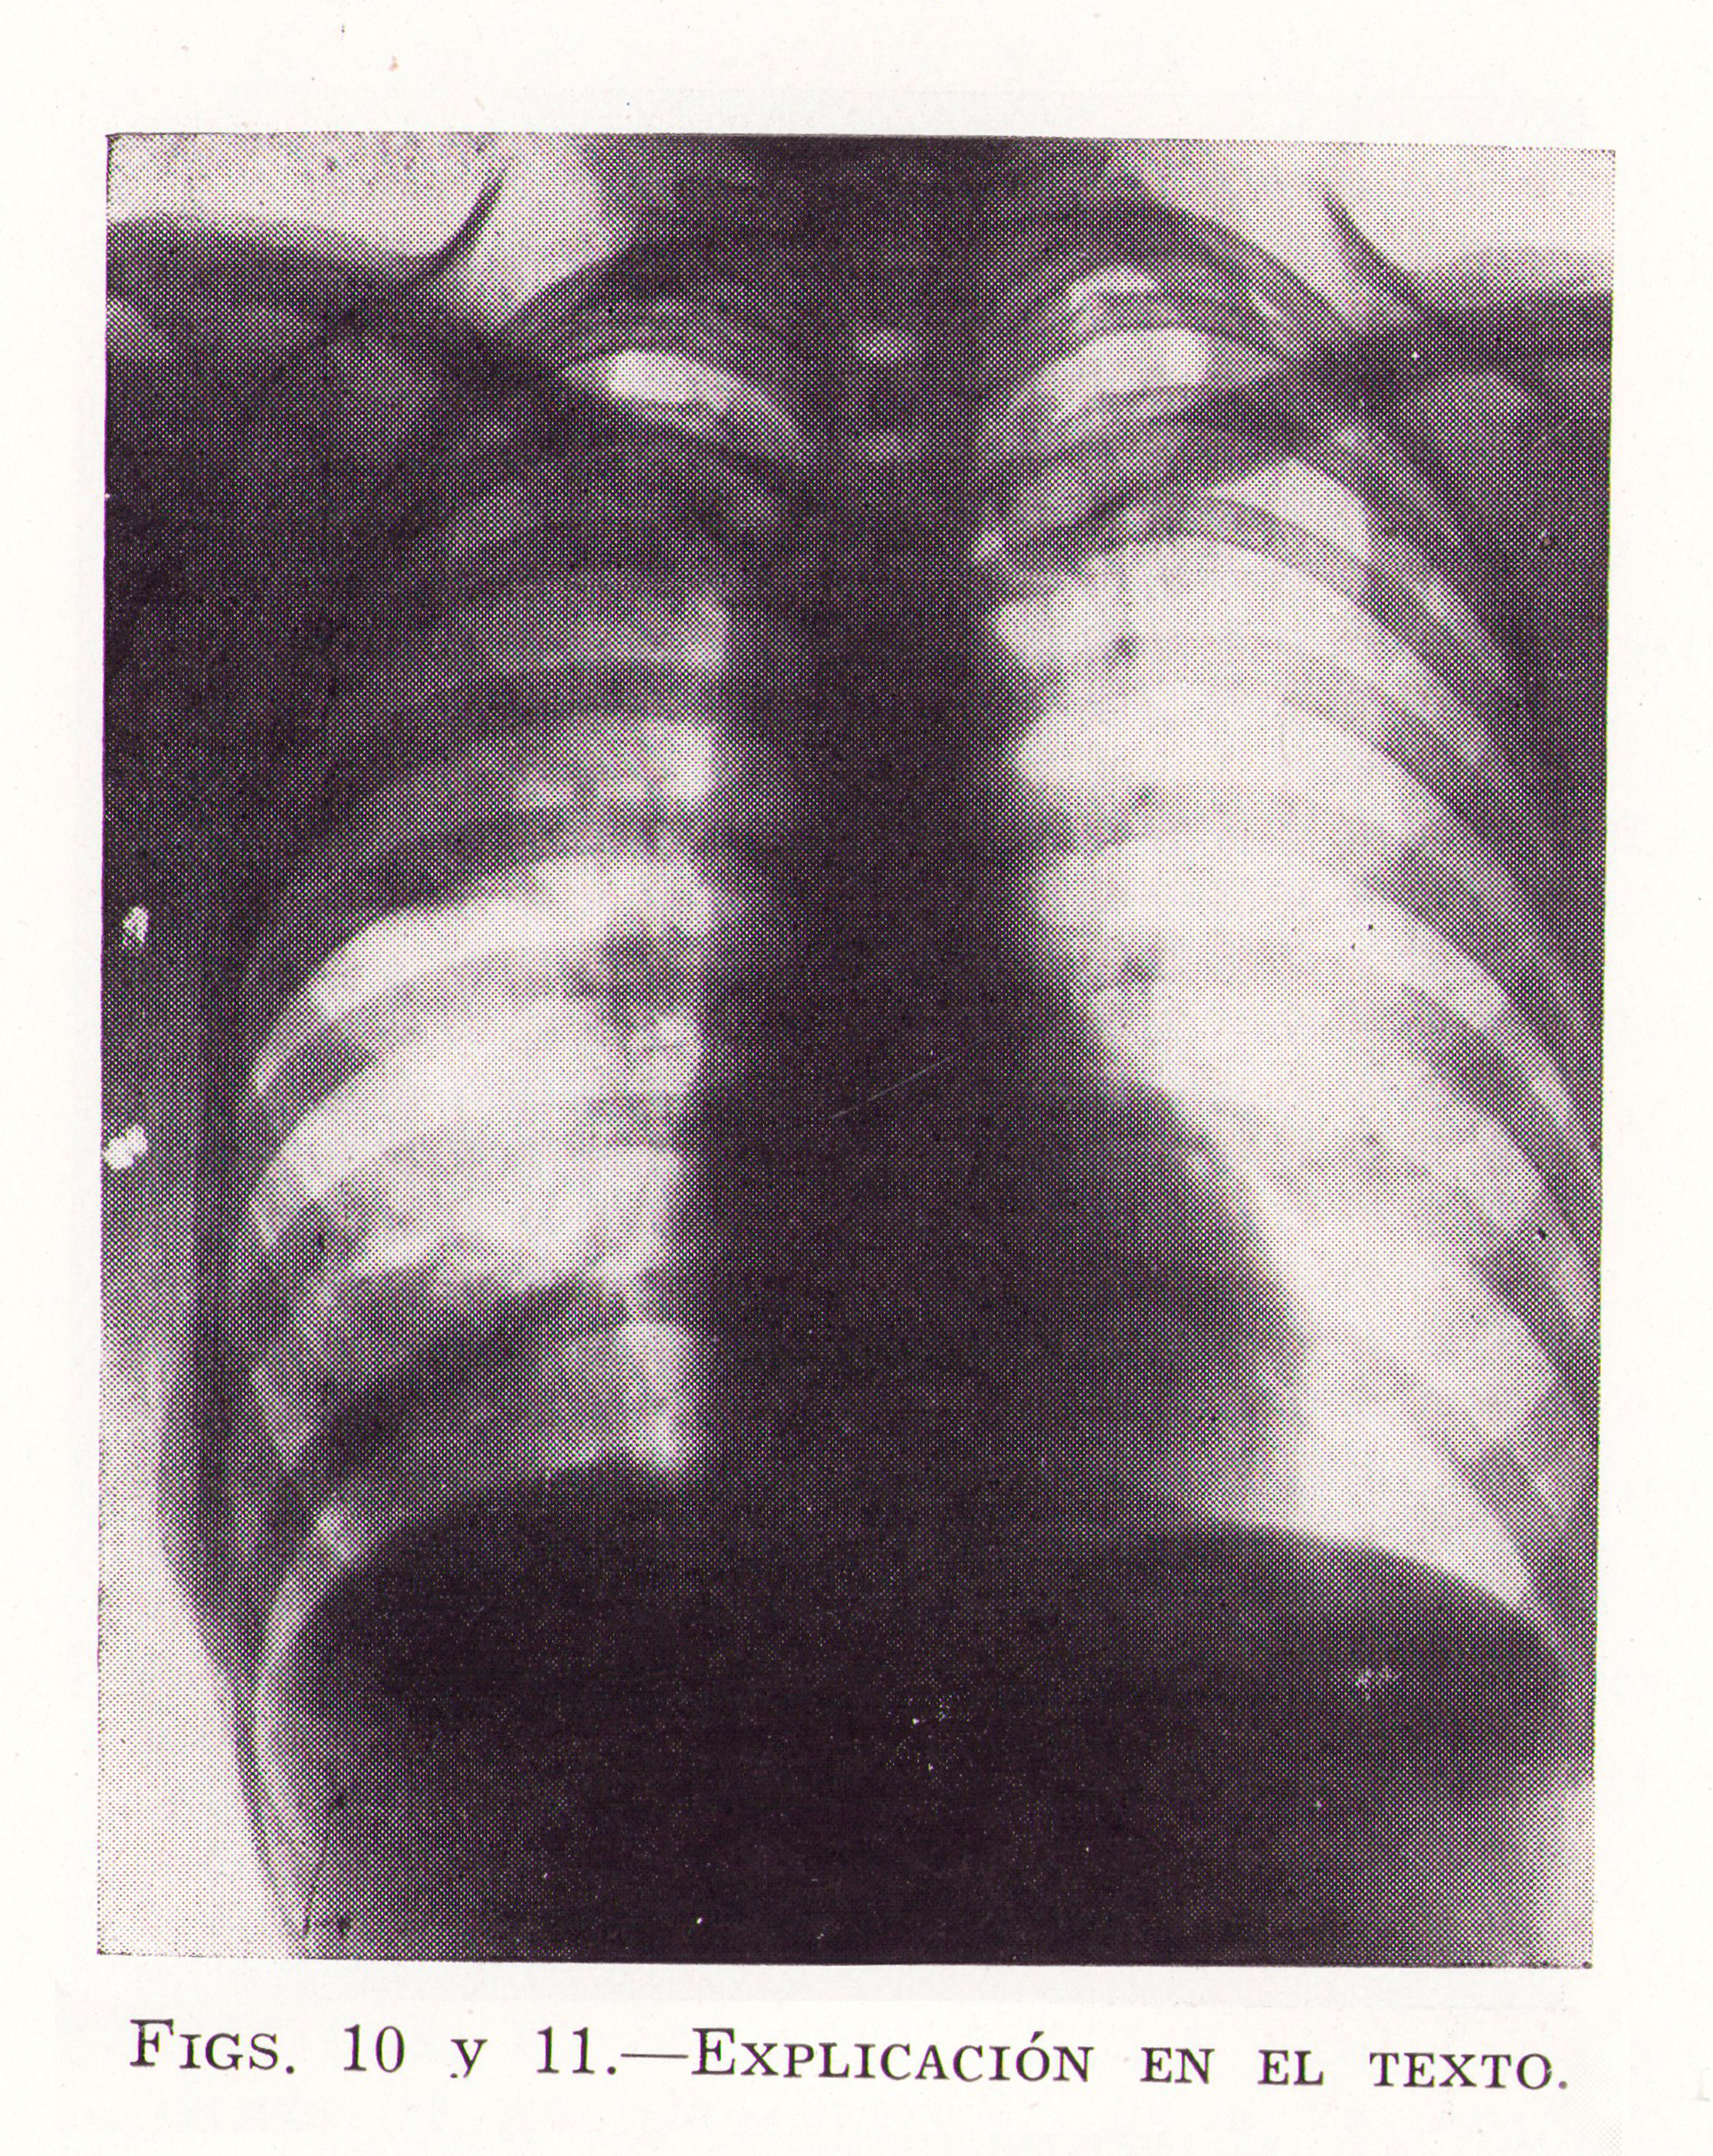

Fig.10. CASO N. 4. Natural de Alconaba (Soria), de 19 años de edad. Tuvo hace dieciocho meses una pulmonía (?): fiebre, tos, dolor de costado y expectoración sanguinolenta. Ingresó en el Hospital el 8-5-1933. Se puso bien, y hace tres meses otra vez los mismos sintomas, durando unos quince días: hace treinta días, sólo expectoración con sangre, que ha seguido hasta la fecha; disnea de esfuerzo, cansancio muscular: ha perdido de peso. Submatidez en base derecha, disminución de murmullos en la misma región. Velocidad de sedimentación, 42 a la hora: 11.600 leucocitos en la fórmula leucocitaria; 2’5 por ciento de eosinófilos, Reacción de Casoni, fuertemente positiva, la precoz y la tardía,

En algunas radioscopias persistió también una pequeña imagen de aclaramiento en parte superior, pero sin los caracteres del neumoquiste perivesicular de Morquio y Bonaba.

Desde septiembre de 1933 hasta diciembre de 1936, este enfermo tuvo diversos accidentes, entre ellos algunos cardiacos de sistema nervioso, que comentamos en otra parte, y expectoración hemoptoica casi constantemente: algunos días de flebre, aunque la mayor parte del tiempo pudo hacer vida normal trabajando en las faenas del campo. De vez en cuando eliminaba algún trozo de membrana. A últimos del año 1936 fué cuando tuvo una hemoptisis de mediana intensidad, fiebre y eliminación de grandes trozos membranosos, que me trajeron y pude confirmar su naturaleza hidatídica. A partir de esta época, el enfermo se encontró muy bien, habiéndole observado periódicamente hasta el año 1942, sin presentar alteraciones en lo que se refiere a pulmón. En el momento actual (mayo de 1951) se encuentra completamente bien. Dieciocho años después del comienzo de la vómica.